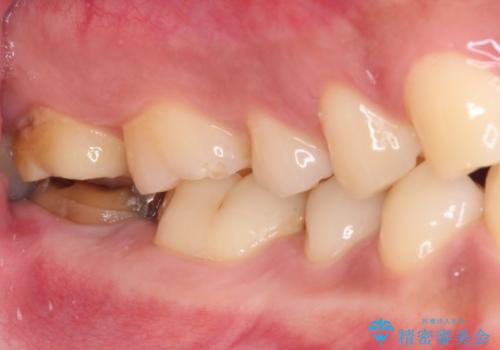

- 奥歯の虫歯治療を希望したものの、歯の高さが足りなくて治療ができないと言われ、来院された患者様です。

レントゲン撮影より、根尖部に病変が認められたため、根管治療を行った後に、歯冠長延長術を行うこととしました。

銀歯の頃は頻繁に外れていたため、不快感が強かったようですが、歯冠長を延長したことで外れにくいクラウンを装着することができ、不快感が改善されました。